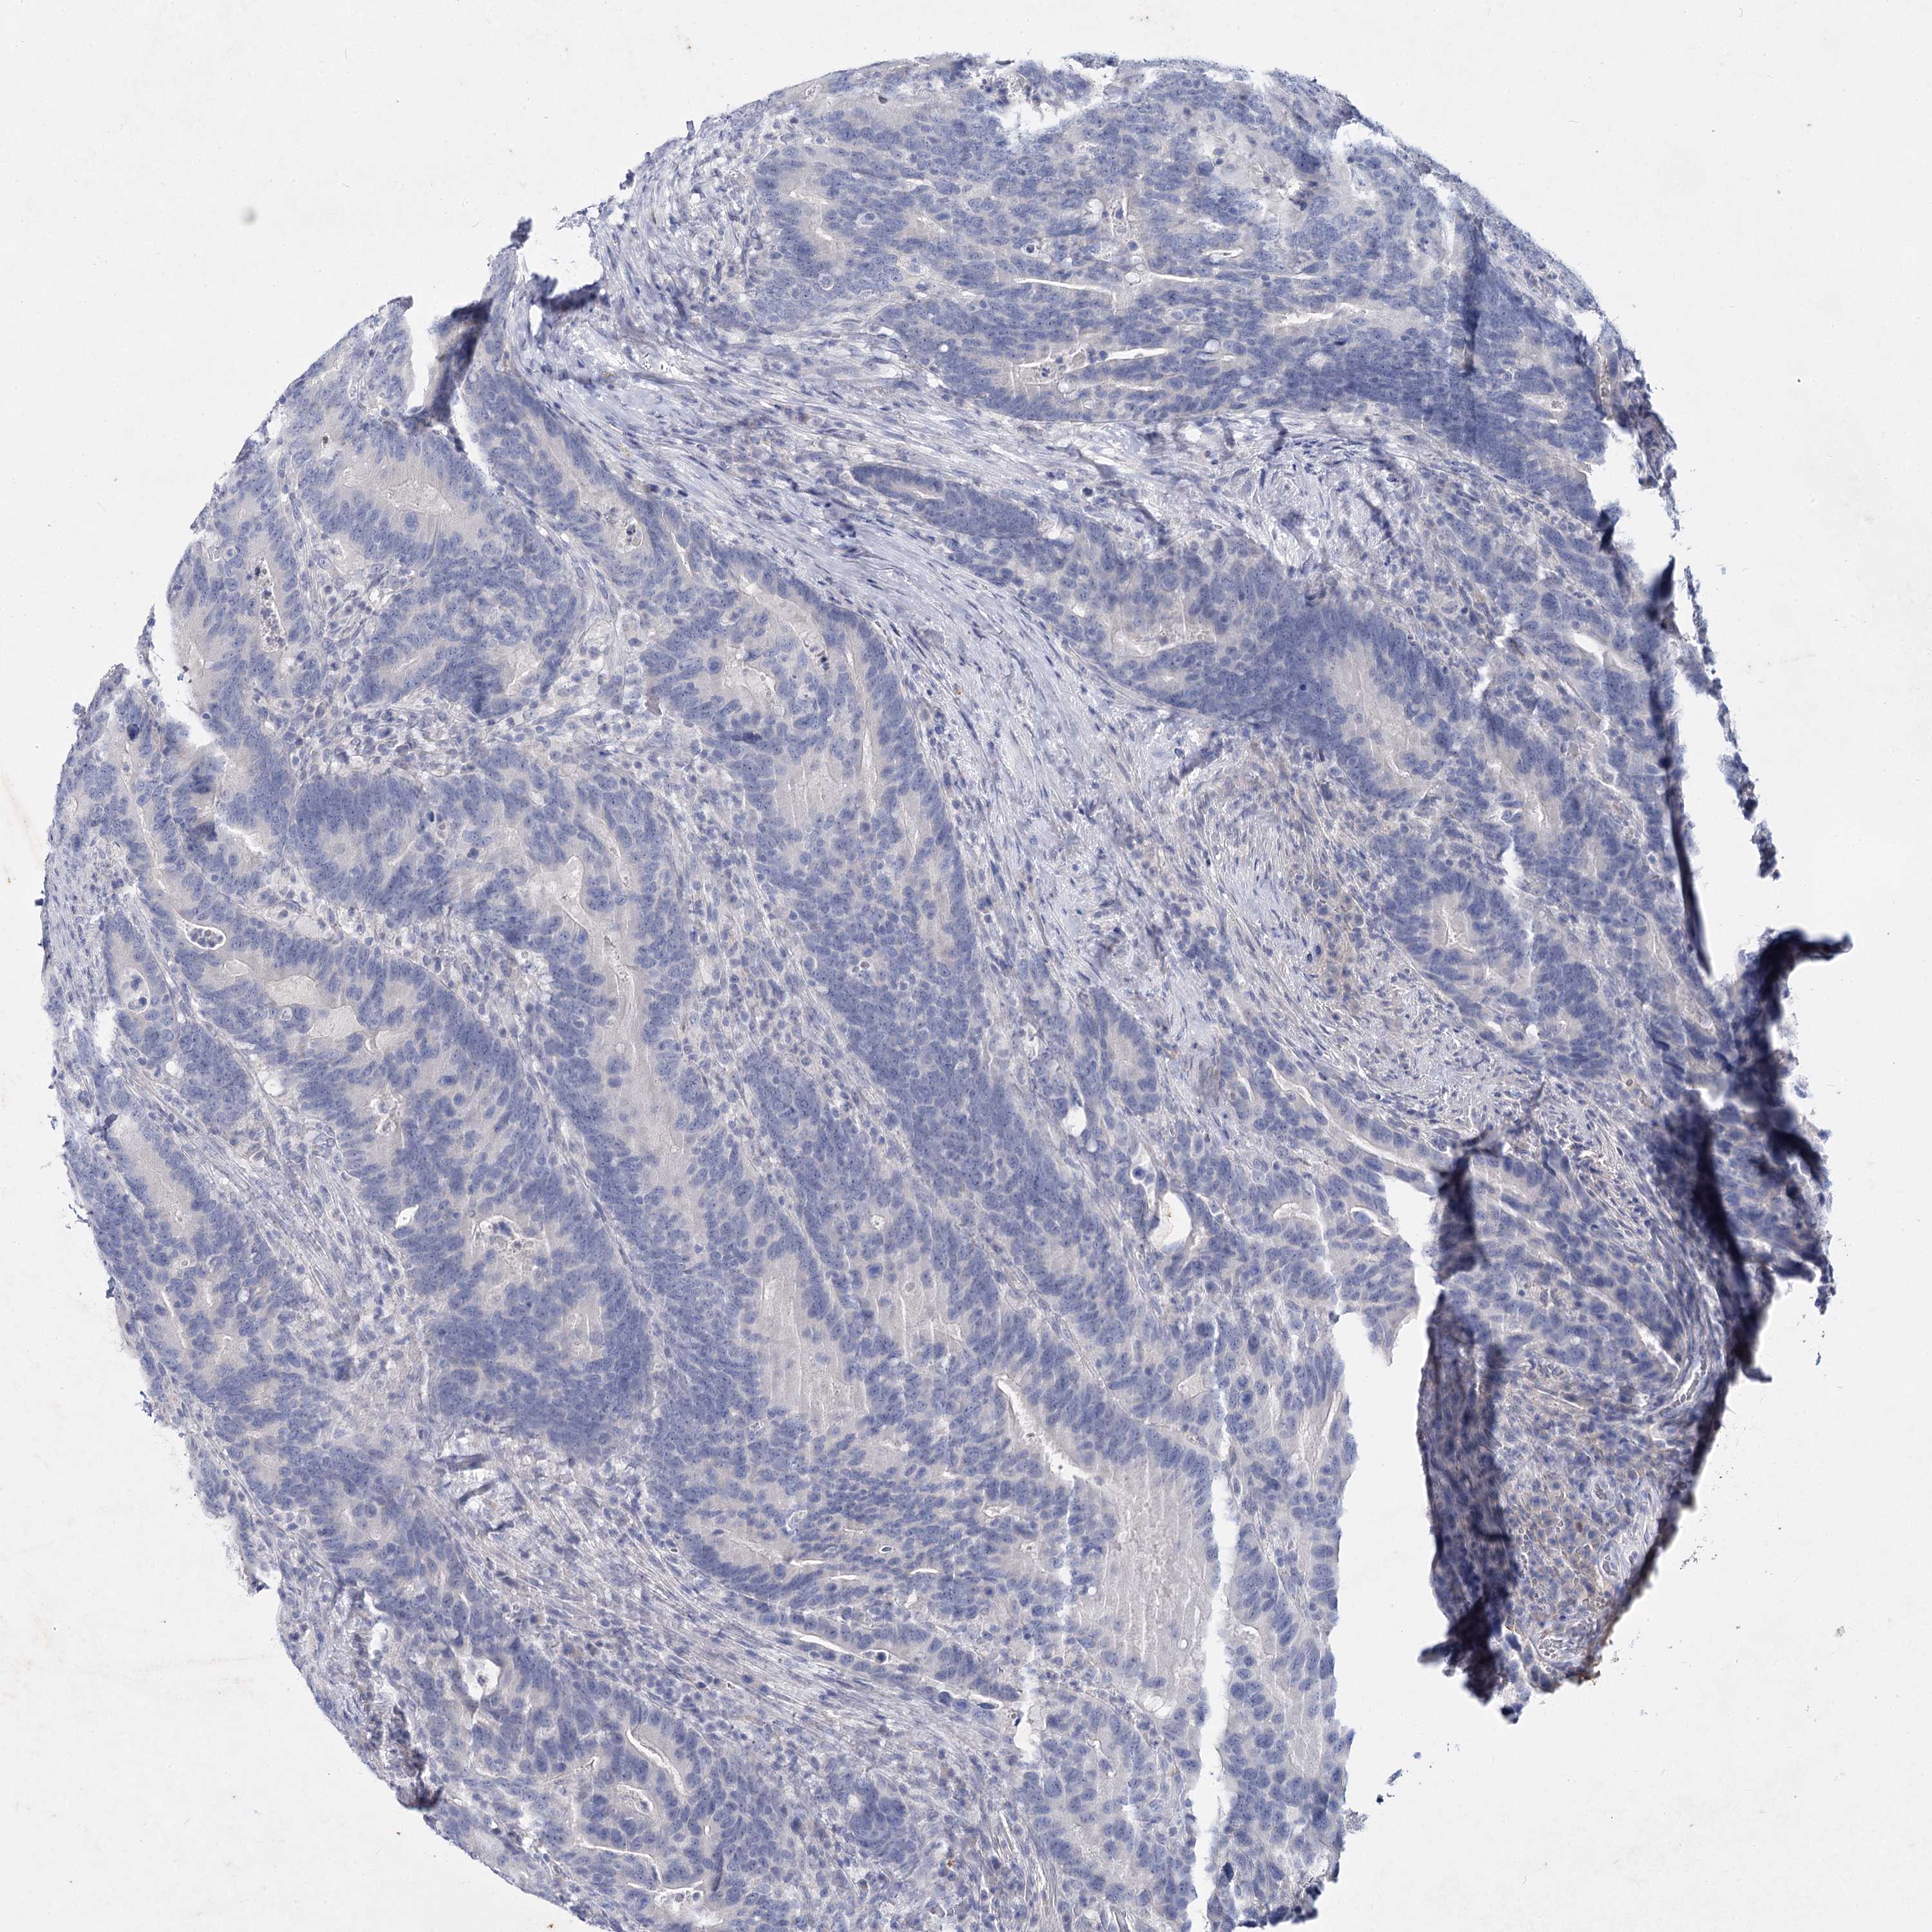

CANCER COLORECTAL CANCER Show tissue menu

Colorectal cancer

Human cancer

Colon adenocarcinoma